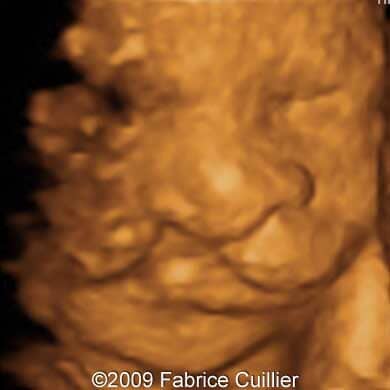

The following images show a case of an unilateral cleft lip diagnosed at 25 weeks old fetus of a 22-year-old mother with non-contributive history. No other anomaly was found. Karyotyping revealed normal karyotype (46,XX) and the course of the pregnancy was uneventful. The neonate was delivered at 38 weeks and its surgery is scheduled at six months.

Images 3, 4, 5: 3D images showing unilateral cleft lip.